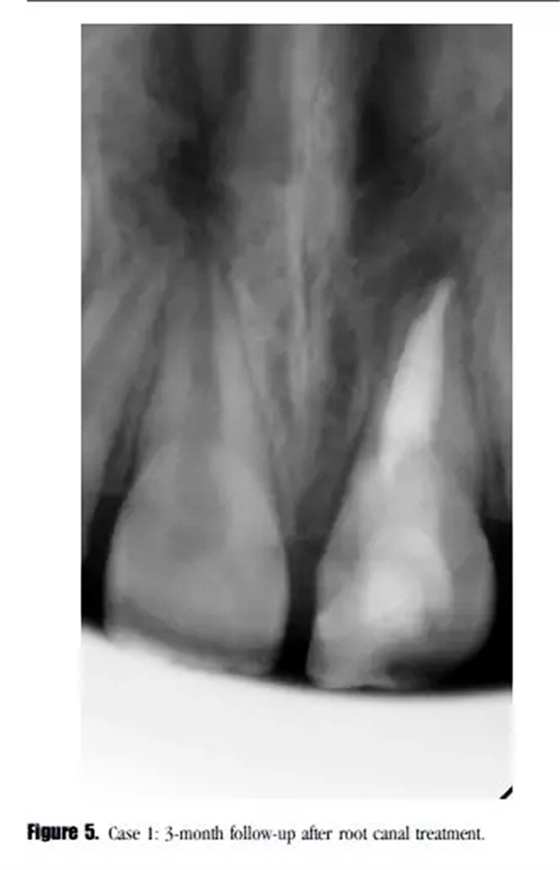

在3個月后的回訪中,患者癥狀消失,X線顯示根尖透射區(qū)域減小。(圖5)